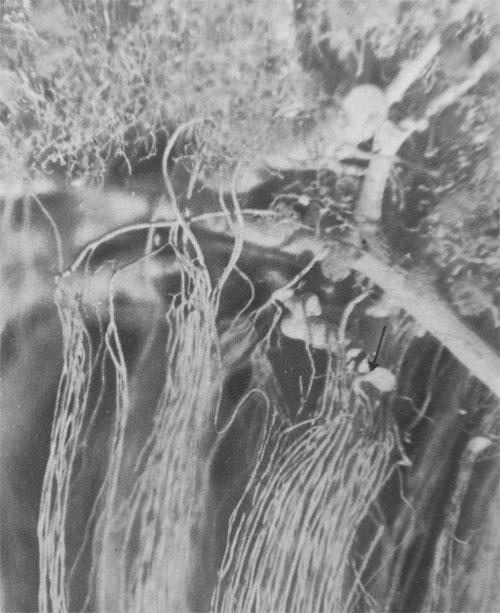

The juxtamedullary efferent arterioles mostly begin on the cortical side of the arcuate vessels so that in order to reach the medulla they or their branches have to sweep around these large vessels on either side, giving a very characteristic appearance (Fig. 1.7).

In the region of the arcuate vessels, the efferent arteriole breaks up abruptly into a bundle of descending vasa recta, each of which is not much smaller than the parent vessel (Figs 1.7, 1.8 and 1.9/Read: The medullary capillaries and Venous drainage of the medulla). There is thus a sudden enormous increase in the total cross-sectional'area of the vessels entering the medulla with, presumably, a corresponding decrease in pressure and flow rate.

Each efferent arteriole may supply vasa recta to a number of bundles and each bundle receives vasa recta from a number of efferent arterioles which sometimes travel a considerable distance to reach the bundle of their choice (Fig. 1.8). In this way, the number of descending vasa recta in the average vascular bundle may be as many as thirty to thirty-dive, but bundles containing fifty or more descending vessels are quite common.